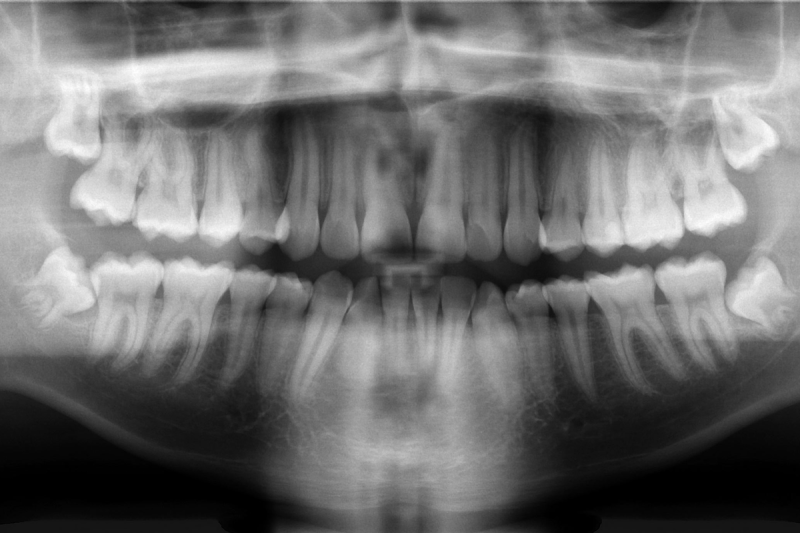

In the course of normal development, humans grow a set of baby teeth, followed by a set of adult or “permanent” teeth. Conventional wisdom tells us that this second set is all we get, and that we should properly care for them if we hope to hang on to them for life. Physical injury can knock them out, and a lack of dental hygiene can see them badly damaged to the point where they have to be removed. Thus, there are plenty of incentives to take care of one’s teeth, given that there is little to be done beyond replacing them with clumsy dentures if they fail us.

Research suggests that humans may have an extra set of teeth “buds” lurking in the jaw that normally lay dormant; it could be as simple as activating them to produce new teeth as needed. Thus, the concept is sometimes referred to as growing “the third tooth”—in that a regenerated tooth would be the third tooth after the original baby and adult teeth. Particularly as human lifespans grow longer, the ability to produce a third set of teeth becomes more valuable. However, the technique won’t just be useful for people that break a tooth or lose one to excessive acid wear or associated damage. Indeed, an early focus of the work is to help individuals with conditions like congenital anodontia, wherein a patient never grew a full set of mature permanent teeth. The aim is that the treatment could stimulate the growth of strong, adult-grade teeth to improve the quality of life for those with the condition.

With early stage trials in mice completed some time ago, the treatment remains in early stage clinical trials for humans. An initial trial tested the treatment on adult males from 30 to 64 years old who were missing at least one tooth. This was with the hope that if growth did occur, it would ideally be limited to the missing slot, rather than causing new growth in areas that would push out existing healthy teeth. The next stage of trials will involve young children from ages 2 to 7 who are missing at least four teeth, to test the treatment on those with a congenital tooth deficiency. It’s likely that testing will also aim to determine just how USAG-1 suppression influences tooth regrowth. Ideally, it would only occur in specific areas where teeth were missing. It would be a great disaster if the treatment led to widespread tooth regrowth, which could cause crowding issues or loss of healthy teeth.